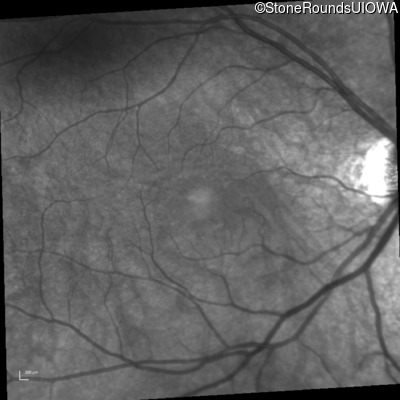

Infrared Fundus Photograph - Left - 20/50

Exemplar